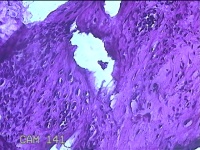

左侧膝部皮下结节

性别

男

年龄

7岁

临床诊断

皮下结节

一般病史

发现左侧膝部皮下结节2年余,无明显疼痛及不适。

标本名称

大体所见

灰白暗红色组织1.5x0.8x0.7cm一块,表面带梭形皮肤1.5x0.8cm,皮下见结节1.5x0.8x0.3cm一个,切开结节呈囊性,囊内有少许清亮液体,囊壁厚0.1cm。